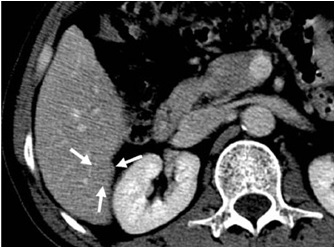

low-low-low (动脉期-门静脉期-平衡期,都为低密度) 51-year-old woman with early hepatocellular carcinoma located in right hepatic lobe 三期均为低密度

Low-Low-Low